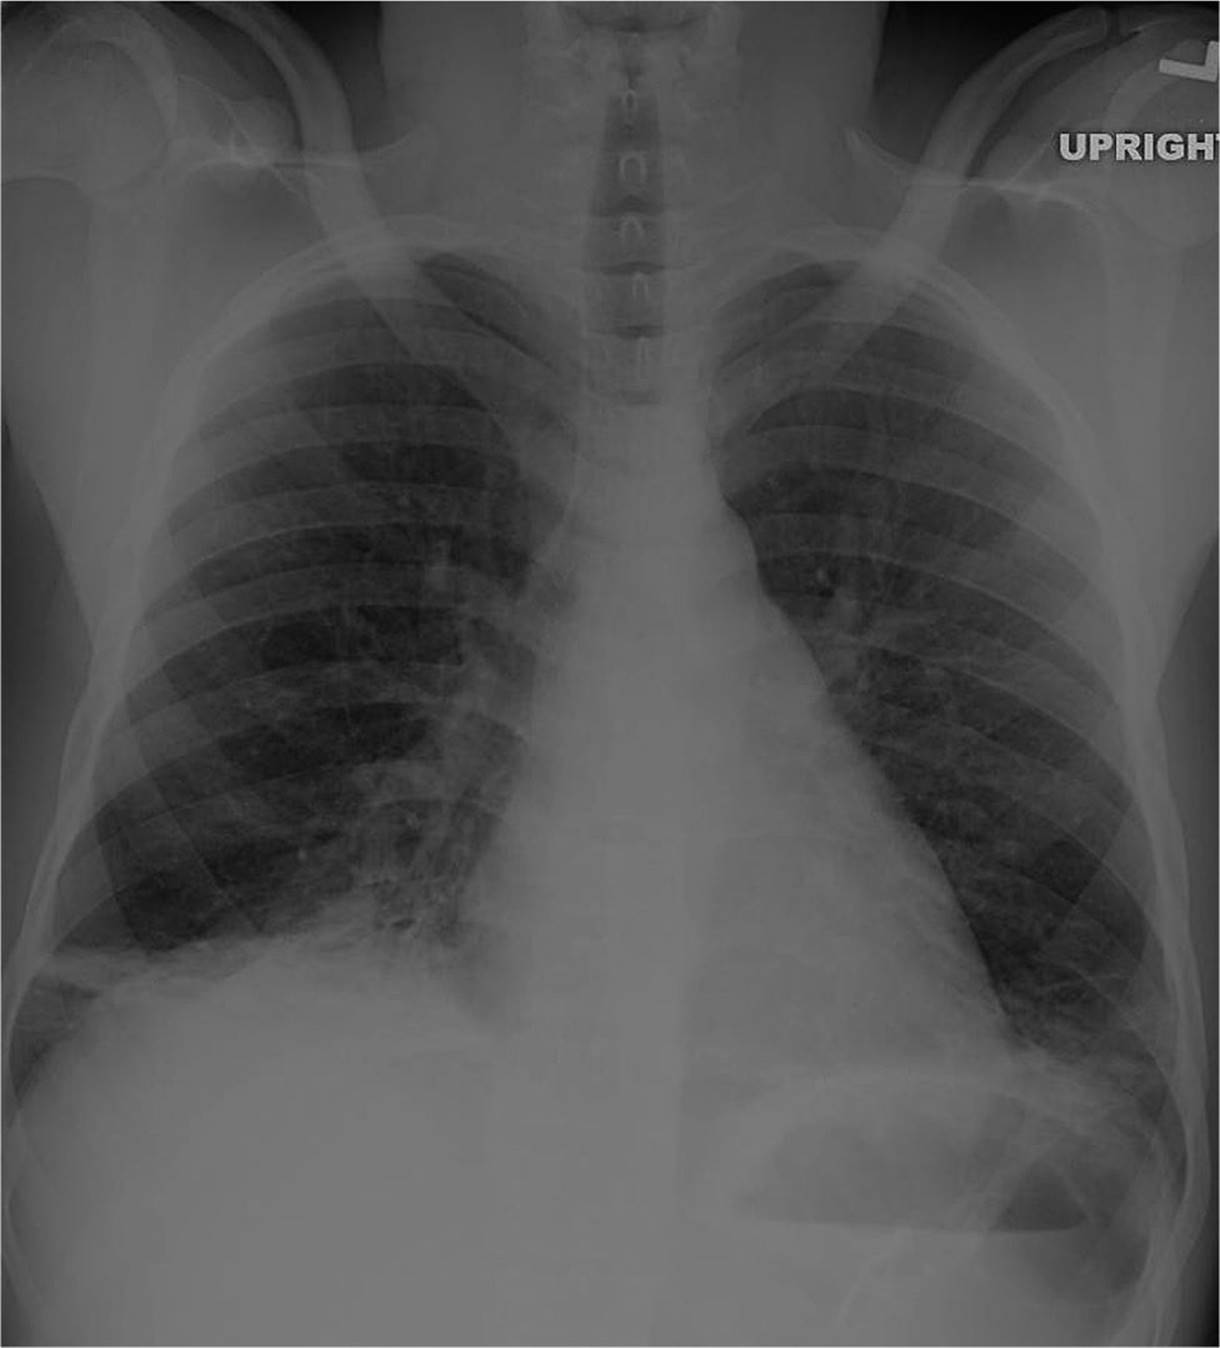

Chest radiographs should be obtained, but may be normal initially (see Fig. 86-2).

FIG. 86-2. Acute chest crisis. (Courtesy of Hollie Jackson, MD.)